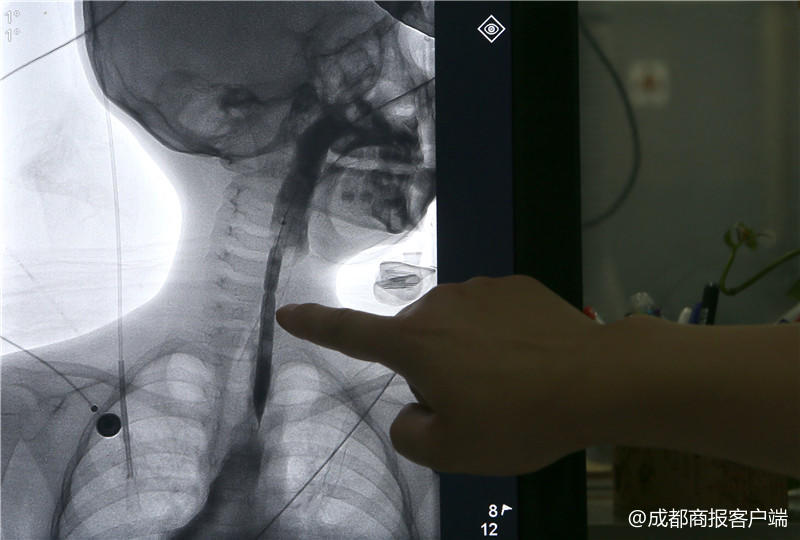

今年4月初,李中贵发现琳琳吃饭的速度越来越慢,而且容易被呛到,于是,李中贵带着琳琳又一次来到成都市妇女儿童中心医院,做了一次检查,发现食道狭窄。5月,琳琳被收治入院。“在门诊做了一个造影,发现食道有狭窄,最窄的地方只有1.8毫米。”琳琳的主治医生、儿外一病区仲铀医生介绍说,琳琳的情况不容轻视。

“我们用的最小的导丝都有3毫米,但是食道最狭窄的地方只有1.8毫米。”仲铀介绍说,只能给琳琳用药,缓解水肿情况和食道上的瘢痕,同时联系了介入科,希望介入科更细微的导管能起到作用。

“挛缩的部位在第4颈椎和第7颈椎位置之间,大约有5厘米长。”赵虎介绍说,检查结果发现,琳琳结肠再造的食道挛缩严重,进食通道十分狭窄,最窄的位置只有1.8毫米。